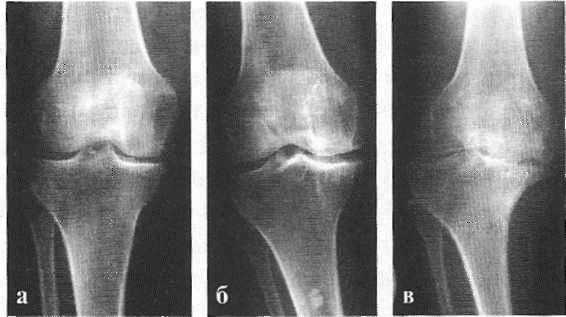

На рентгенограмме обоих коленных суставов в двух проекциях: резко выраженные краевые остеофиты суставных концов, межмыщелковых возвышений и надколенников, значительное сужение ретропателлярных пространств, суставные щели сужены. Уплотнены связки надколенника, что рентгенологически соответствует деформирующему артрозу III степени — ФН 3.

Классификация и стадии развития артроза коленных суставов

Независимо от причины возникновения выделяют три стадии заболевания гонартроза, или деформирующего артроза коленного сустава.

Гонартроз, I стадия

Первая стадия заболевания характеризуется первичными изменениями в гиалиновом хряще. [12] [18] Костные структуры не затрагиваются. Во внутрикостных сосудах и капиллярах нарушается кровоснабжение. Становится сухой поверхность хряща, и он утрачивает свою гладкость. Если заболевание сопровождается постоянным напряженным синовитом, то развивается киста Бейкера (грыжевое выпячивание капсулы сустава подколенной области). [15] После значительной нагрузки на сустав возникают тупые боли. Возможна небольшая отечность, которая проходит после отдыха. Деформации нет.

Гонартроз, II стадия

На второй стадии хрящевая прослойка резко истончается, а местами и вовсе отсутствует. [22] Появляются остеофиты по краям суставных поверхностей. Изменяются качественные и количественные характеристики синовиальной жидкости сустава — она становится гуще, более вязкой, что приводит к ухудшению питающих и смазывающих свойств. [14] [16] Боли более продолжительные и интенсивные, часто при движении появляется хруст. Отмечается незначительное или умеренное ограничение движений и небольшая деформация сустава. Прием анальгетиков помогает снять болевой синдром.

Гонартроз, III стадия

Отсутствие хряща на большинстве поражённых участков, выраженный склероз (уплотнение) кости, множество остеофитов и резкое сужение или отсутствие суставной щели. [8] [15] Боли практически постоянные, походка нарушена. Подвижность резко ограничена, заметна деформация сустава. Препараты НПВС, физиопроцедуры и другие стандартные методы лечения артроза коленного сустава неэффективны. [11]